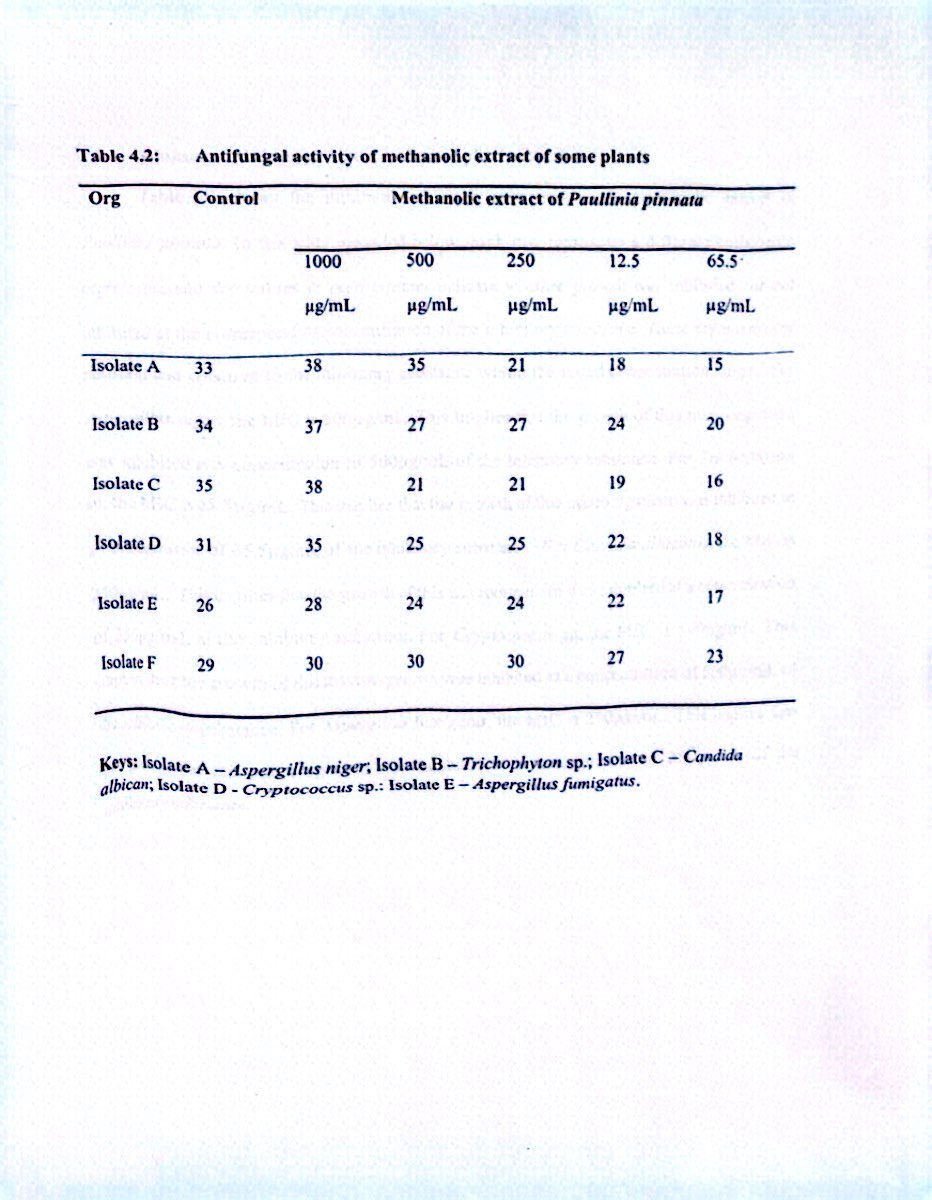

Thin Layer Chromatography,ultraviolet Absorption Spectral Characteristics and Biological Activity of Paullinia Pinata Methanolic Extract